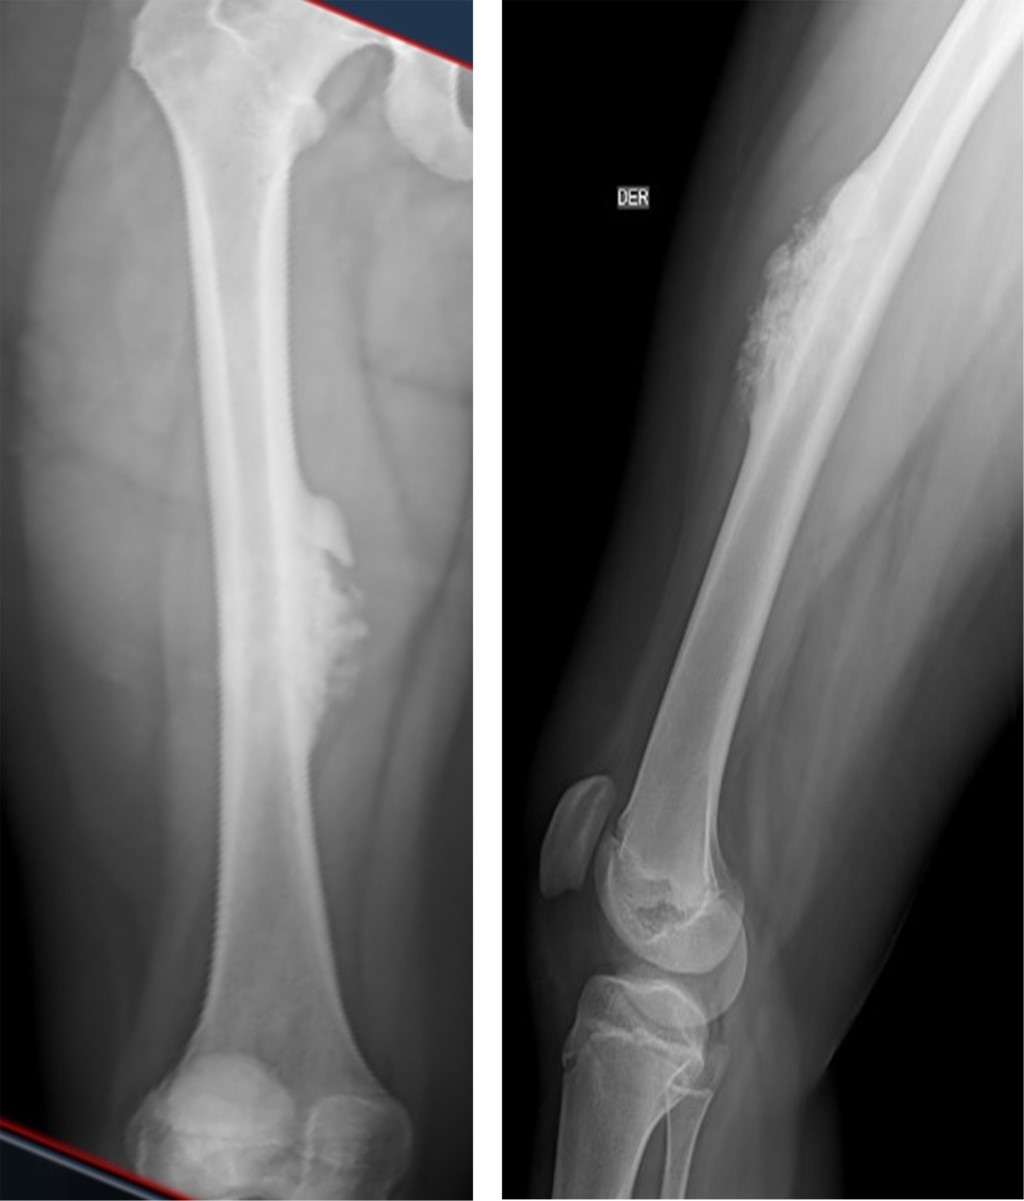

Se realizan radiografías de fémur derecho, donde se observa lesión ósea a nivel de tercio medio de diáfisis femoral, de bordes irregulares, con reacción perióstica en cortical anteromedial que mostraba zonas escleróticas con una zona de transición bien definida (Figura 1). En tomografía axial computarizada (TAC) de miembros pélvicos de Septiembre de 2021, se encuentra lesión ósea irregular en tercio medio de fémur derecho, en cara anteromedial, con patrón de esclerosis y osteólisis. Se realiza primera biopsia percutánea en quirófano en Septiembre de 2021, la cual es enviada a patología donde se reporta muestra insuficiente; se solicita valoración por el Servicio de Oncología Pediátrica, quien, ante resultado negativo, solicita nueva biopsia para normar conducta.

Figura 1